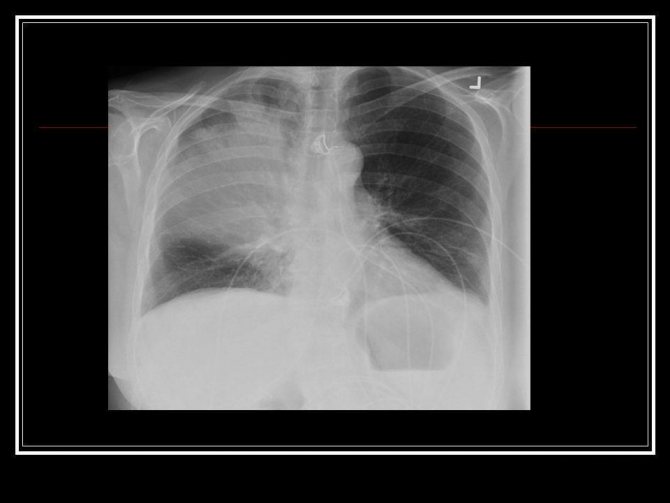

Во многих случаях клиническая симптоматика приходит позже, чем проявляются изменения на рентгенограмме. При выраженных иммунодефицитах возникает необходимость в диагностике совсем небольших очагов при помощи метода компьютерной томографии.

Симптомы атипичной пневмонии у взрослых и детей малоспецифичны. Диагноз в основном подтверждается при исследовании биологического материала пациента, который направляется на исследование сразу же, как только врачу становится понятно, что классический протокол лечения эффекта не даёт. Во многих случаях на рентгенологическом снимке просматривается воспалительный процесс в лёгких, но стандартная терапия никакого эффекта не даёт.

Атипичная легионеллезная пневмония на рентгеновском снимке